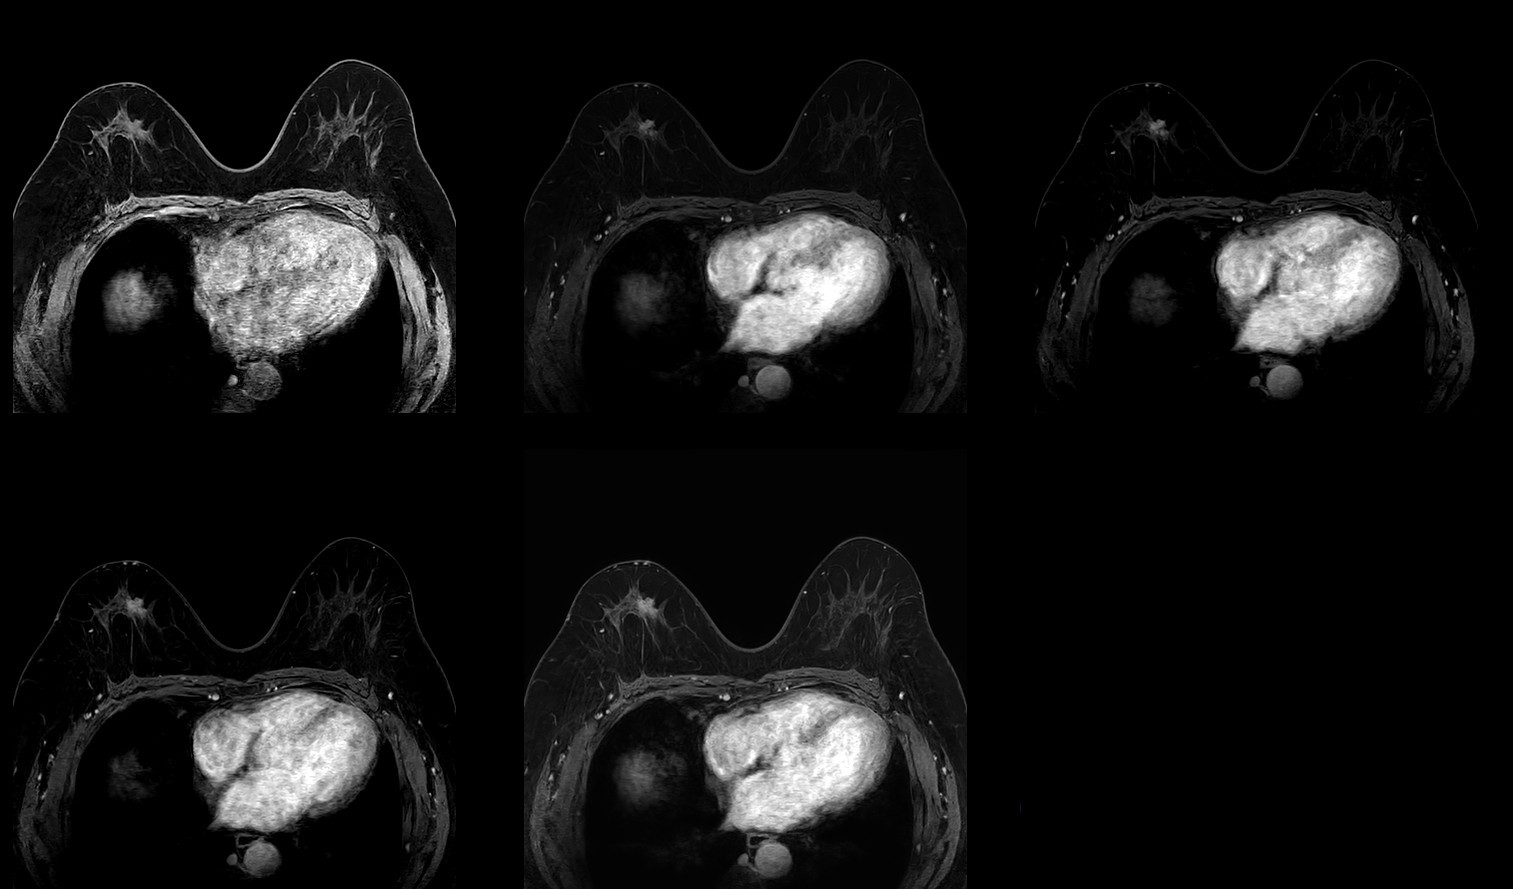

Dynamic T1w TFE